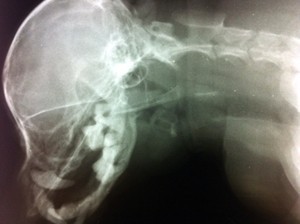

Pewnego dnia podeszła do naszego gabinetu Pani i w drzwiach zadała nam pytanie: jak pies się dusi kością od wczoraj to co ma zrobić? Prawie chórem wykrzyknęliśmy, że natychmiast przyjść do gabinety. Taka kość nie tylko może przebić przełyk czy gardło, ale spowodować głęboki uraz zagrażający życiu.

Staraliśmy się wyjaśnić powagę problemu, ale Pani skwitowała nas, "że ona jeszcze popróbuje domowymi sposobami".

Istotnie zjawiła się dzień później z otyłym Yorkiem.